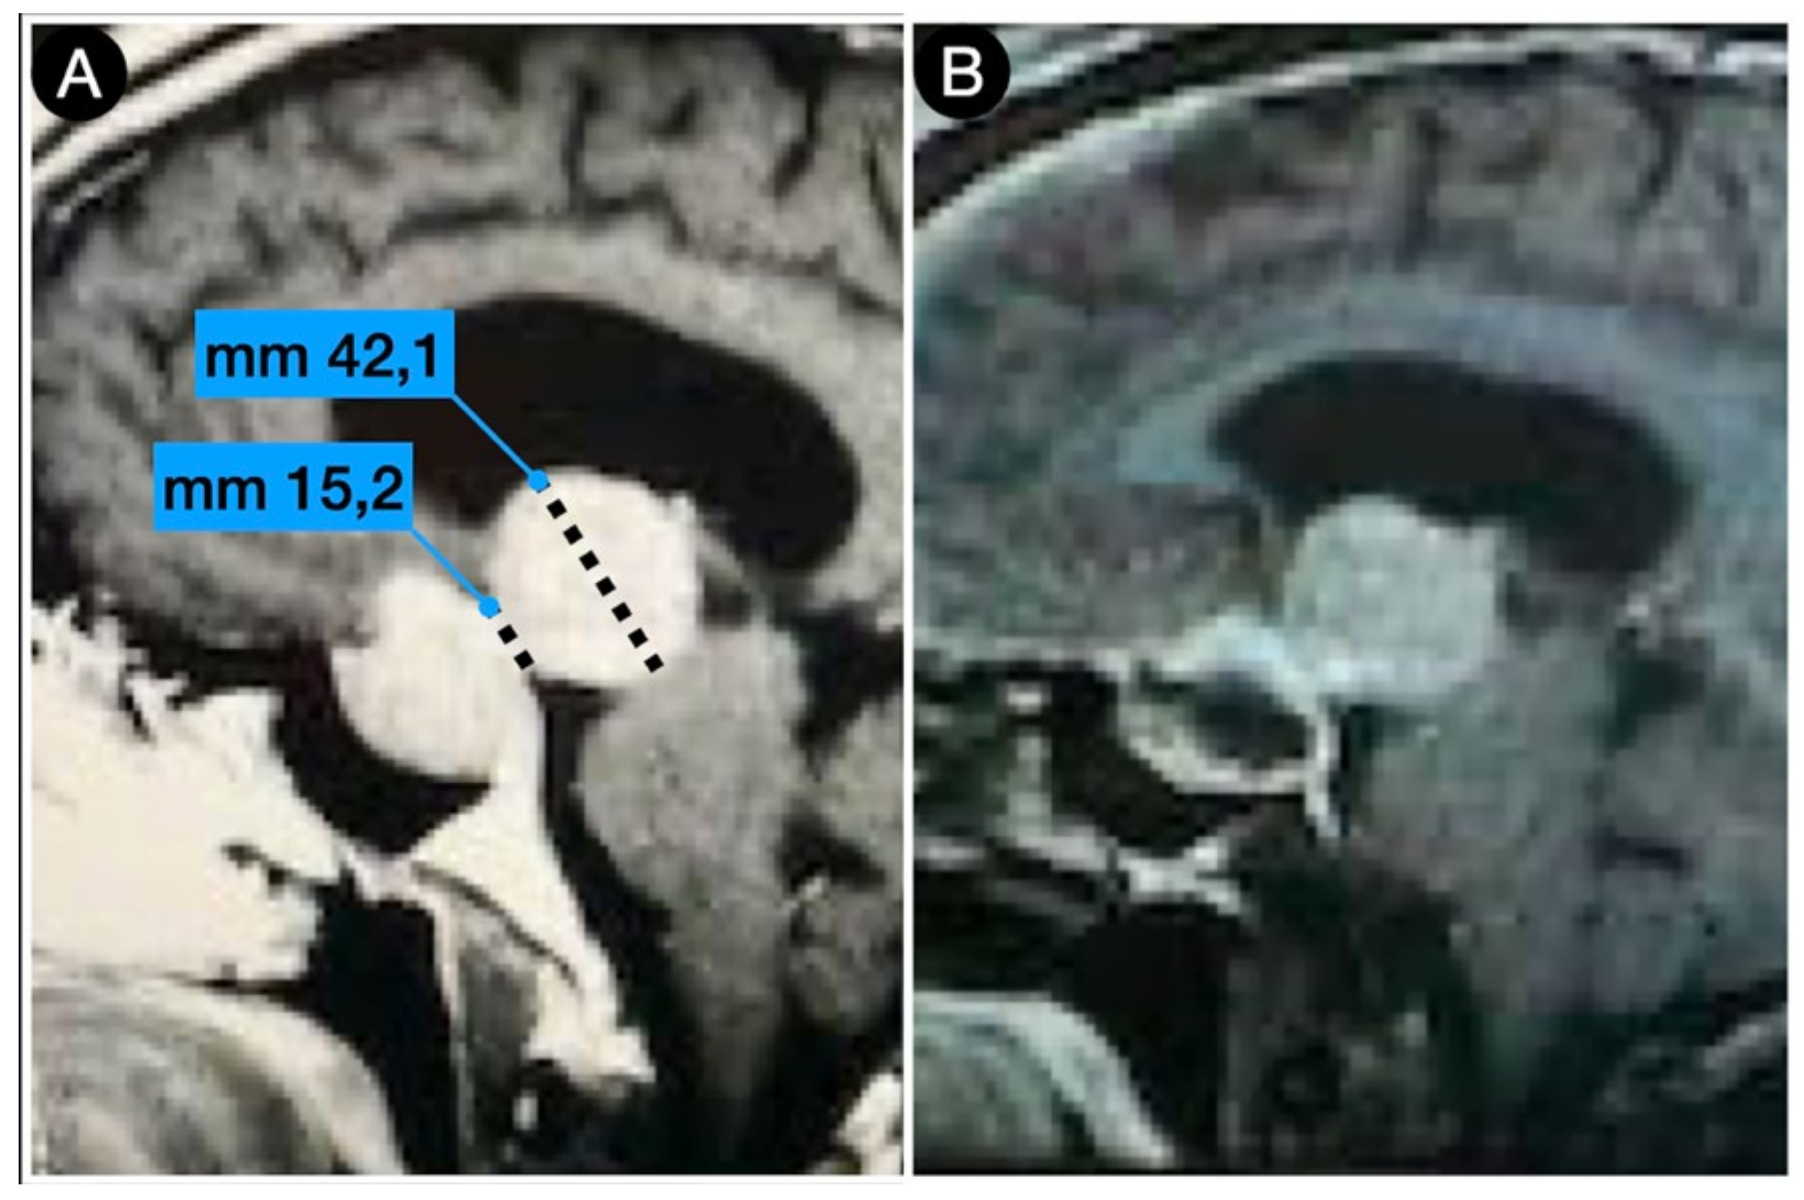

2.5. Anatomy of The Sellar Diaphragm

Case #1: Infradiaphragmantic Tumor with Middle Fossa Involvement through the Cavernous Sinus